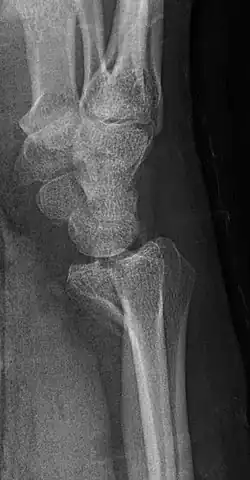

Lateral projectional radiograph of the same fracture

A Barton's fracture is a type of wrist injury where there is a broken bone associated with a dislocated bone in the wrist, typically occurring after falling on top of a bent wrist.[1] It is an intra-articular fracture of the distal radius with dislocation of the radiocarpal joint.[2]

There exist two types of Barton's fracture – dorsal[3] and palmar, the latter being more common. The Barton's fracture is caused by a fall on an extended and pronated wrist increasing carpal compression force on the dorsal rim. Intra-articular component distinguishes this fracture from a Smith's or a Colles' fracture. Treatment of this fracture is usually done by open reduction and internal fixation with a plate and screws, but occasionally the fracture can be treated conservatively.[4]